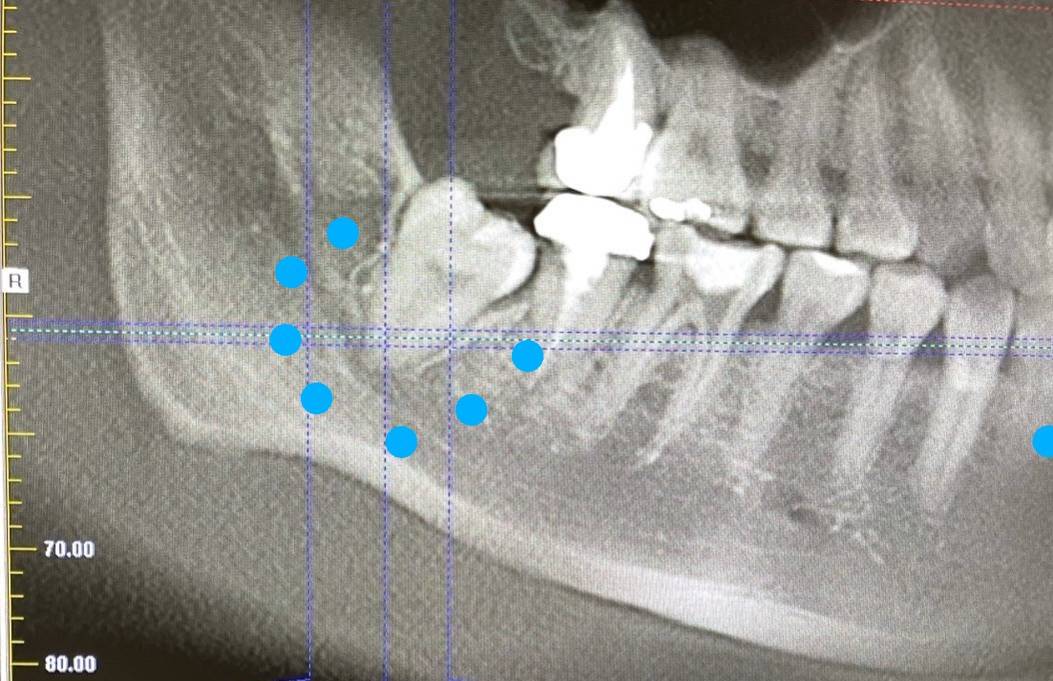

智齒長歪壓迫下齒槽神經管,導致王小姐右下巴臉頰、嘴唇周圍的麻痺及疼痛感。圖:聖保祿醫院提供

徐偉軒進一步說明,檢查後發現王小姐右下巴的第三大臼齒為深層埋伏的阻生齒,換句話說就是智齒長歪,智齒牙根靠近下齒槽神經管,長歪的智齒已經壓迫到右側下齒槽神經管,導致王小姐右下巴臉頰、嘴唇周圍的麻痺及疼痛感,而智齒萌發路徑受阻,也可能反向使牙根對神經更壓迫,加劇不舒服症狀,臨床上很少見像王小姐這樣的個案。